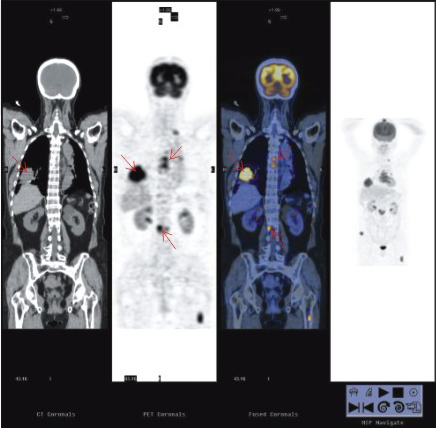

PET-CT一次全身掃描能同時(shí)獲得PET與CT兩者的全身各方位的斷層顯像,它便于病灶的準(zhǔn)確定性和精確定位,便于一目了然了解全身的整體狀況,這對(duì)腫瘤等全身性疾病的診斷、分級(jí)分期和治療方案的制定以及腫瘤原發(fā)病灶的尋找和轉(zhuǎn)移與復(fù)發(fā)的診斷尤為有利。